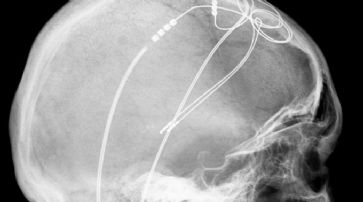

Hilft «Hirnschrittmacher» gegen Drogensucht?

Genf - Die tiefe Hirnstimulation, die bereits gegen verschiedene psychische und neurologische Leiden zum Einsatz kommt, könnte möglicherweise auch die Kokain-Abhängigkeit wirksam behandeln. Dies berichten Genfer Forscher im Fachblatt «Science».

Die zerebrale Tiefenstimulation wurde vor fast 30 Jahren von Pierre Pollak, heute Professor am Departement für Klinische Neurologie an der Universität Genf und Chefarzt der Neurologie am Genfer Universitätsspital (HUG), mitentwickelt. Das Verfahren wird mittlerweile bei rund 100'000 Personen erfolgreich angewendet, auch in der Schweiz.

Von den Gesundheitsbehörden ist die tiefe Hirnstimulation weltweit vor allem zur Behandlung der Parkinson-Krankheit zugelassen. Die umgangssprachlich oft als «Hirnschrittmacher» bezeichnete Methode stimuliert bestimmte Hirnstrukturen mit einem leichten elektrischen Impuls.

Allerdings fehlt es der Technik noch an Präzision: So ist es nicht möglich, gezielt einzelne Zellen zu stimulieren und gleichzeitig ihre unmittelbaren Nachbarzellen zu verschonen. Die Neurowissenschaftler der Universität Genf haben versucht, die Methode zu verbessern, um das Suchtverhalten von Mäusen zu unterdrücken.

Tiefe Hirnstimulation. (Symbolbild) /